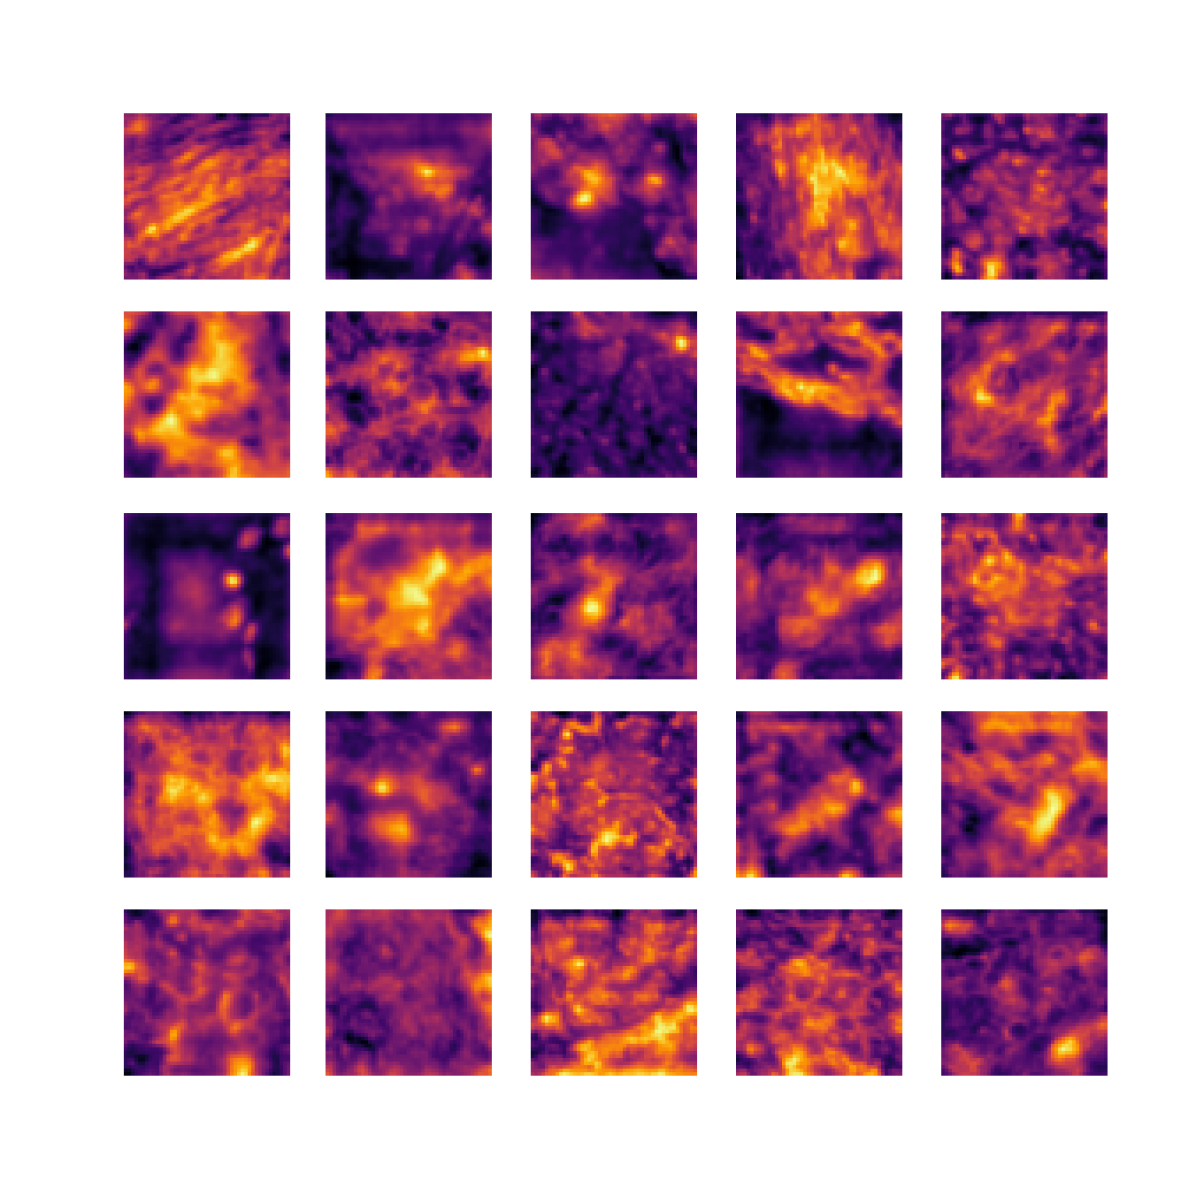

We also analyse the activation maps for each model using GradCAM as described in section S3. This offers more insight into the areas of the image which are contributing most heavily to the models’ representations. In Figure 4(b) we present some representative examples, however, a larger selection which was chosen at random is presented in Figures S10 to S25. The larger selection makes it easier to see the emergent patterns, including that privileged Siamese models tend to mainly identify features which are strongly present in both inputs, while unprivileged Siamese models tend to learn more diffuse features that are not specific to one cell phenotype or image region. TriDeNT ♆ incorporates both sets of features, learning both features specific to the privileged data and more the general features associated with unprivileged Siamese networks.

We can see in Figure 4(b) panel A that for ERG, the privileged Siamese model focuses almost exclusively on any nuclei which could be endothelial cells. As there are very few endothelial cells in the dataset, it could be an effective strategy to identify anything that could potentially be an endothelial cell to minimise the difference between the representations of the H&E model and the IF mask model. In the corresponding unprivileged Siamese image, we see that the model identifies some of these nuclei, albeit less strongly, but also focuses heavily on the other tissue and even the background, while strongly fixating on two spots of debris in the center of the image. This model has less ‘incentive’ to learn the weak features related to endothelial cells as these occur rarely and are not easy to detect, while more generic strong features such as the presence of connective tissue and the prevalence of background are more common and predictable from augmented images. We see that TriDeNT ♆ combines these two feature sets, strongly identifying nuclei while also identifying the connective tissue.

In panel C we see a similar pattern, with the privileged Siamese model fixating solely on the nuclei, while the TriDeNT ♆ model takes a more balanced approach. The unprivileged Siamese model appears to focus on a single cluster of nuclei while neglecting others, and similarly identifies an area of fibroblasts with its distinctive pattern but does not others.

In contrast to panels A and C which represent models with poor privileged Siamese results, panels B and D represent models whose privileged Siamese results were comparable to both TriDeNT ♆ and even the supervised baseline. It is therefore interesting to note that there are far more similarities between the privileged Siamese and TriDeNT ♆ models in both cases. Particularly in panel B, TriDeNT ♆ and the privileged Siamese model return virtually identical heatmaps, with both strongly identifying epithelial nuclei and neglecting the same areas of connective tissue. The unprivileged model in this case appears to focus solely on the centre of the image, giving a significantly different heatmap to the other panels.

Panel D again shows the previous pattern, with the privileged Siamese model identifying the features strongly present in the privileged data – fibroblasts – while neglecting the nuclei present. TriDeNT ♆ also strongly identifies the connective tissue, but, unlike the privileged Siamese model, does not completely neglect the nuclei. The unprivileged Siamese model primarily identifies background, and does not appear to identify the nuclei in this example.